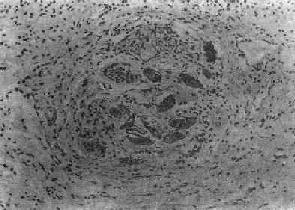

(1)急性虫卵结节:肉眼观为灰黄色、粟粒至绿豆大(0.5~4mm)的小结节。镜下见结节中央常有1~2个成熟虫卵,也偶可多达20个以上。这些成熟虫卵的卵壳上附有放射状嗜酸性的棒状体,也称为Hoeppli现象,用免疫荧光法已证实为抗原抗体复合物。虫卵周围是一片无结构的颗粒状坏死物质及大量嗜酸性粒细胞浸润。因其病变类似脓肿,故也称为嗜酸性脓肿(图19-5)。在坏死组织中可混杂多数菱形或多面形屈光性蛋白质晶体,即Charcot-Leyden结晶,系嗜酸性粒细胞的嗜酸性颗粒互相融合而成。随后虫卵周围产生肉芽组织层,其中有以嗜酸性粒细胞为主的炎症细胞浸润,还有单核巨噬细胞、淋巴细胞、浆细胞及少量中性粒细胞。随着病程的发展,肉芽组织层逐渐向虫卵结节中央生长,并出现围绕结节呈放射状排列的类上皮细胞层。类上皮细胞层逐渐加宽,嗜酸性粒细胞显著减少,构成晚期急性虫卵结节(图19-6),这是向慢性虫卵结节发展的过渡阶段。

血吸虫病之晚期急性虫卵结节

图19-6 血吸虫病之晚期急性虫卵结节

坏死区及嗜酸性粒细胞浸润范围缩小,其周围出现放射状排列的类上皮细胞层